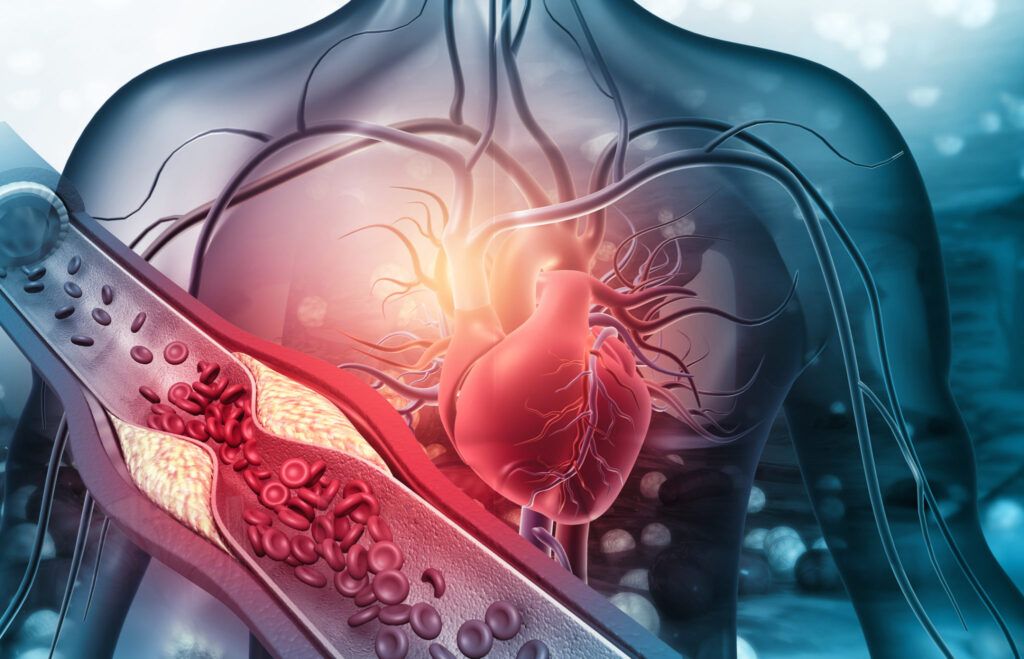

Ateroscleroza, o boală silențioasă care poate conduce la infarct sau accident vascular cerebral, poate fi prevenită prin decizii simple luate zilnic. Potrivit medicilor, înțelegerea factorilor de risc și adoptarea unui stil de viață sănătos reprezintă pași cruciali în protejarea sănătății inimii. Nu mai există scuze, în 2026, accesul la informație este generalizat.

Ateroscleroza, caracterizată prin acumularea de plăci de grăsime pe pereții arterelor, este o afecțiune complexă. Factorii de risc sunt multipli și includ elemente asupra cărora avem influență directă, dar și altele asupra cărora nu putem interveni. Dintre factorii controlabili, alimentația bogată în grăsimi saturate și trans, fumatul, lipsa de activitate fizică și consumul excesiv de alcool joacă un rol major.

Hipertensiunea arterială, diabetul zaharat și nivelul ridicat de colesterol cresc, de asemenea, riscul de afecțiuni cardiovasculare. Pe de altă parte, vârsta, istoricul familial de boli cardiovasculare și sexul (bărbații sunt mai predispuși) sunt factori de risc care nu pot fi modificați. Este esențial să fim conștienți de acești factori, pentru a putea lua măsuri preventive.